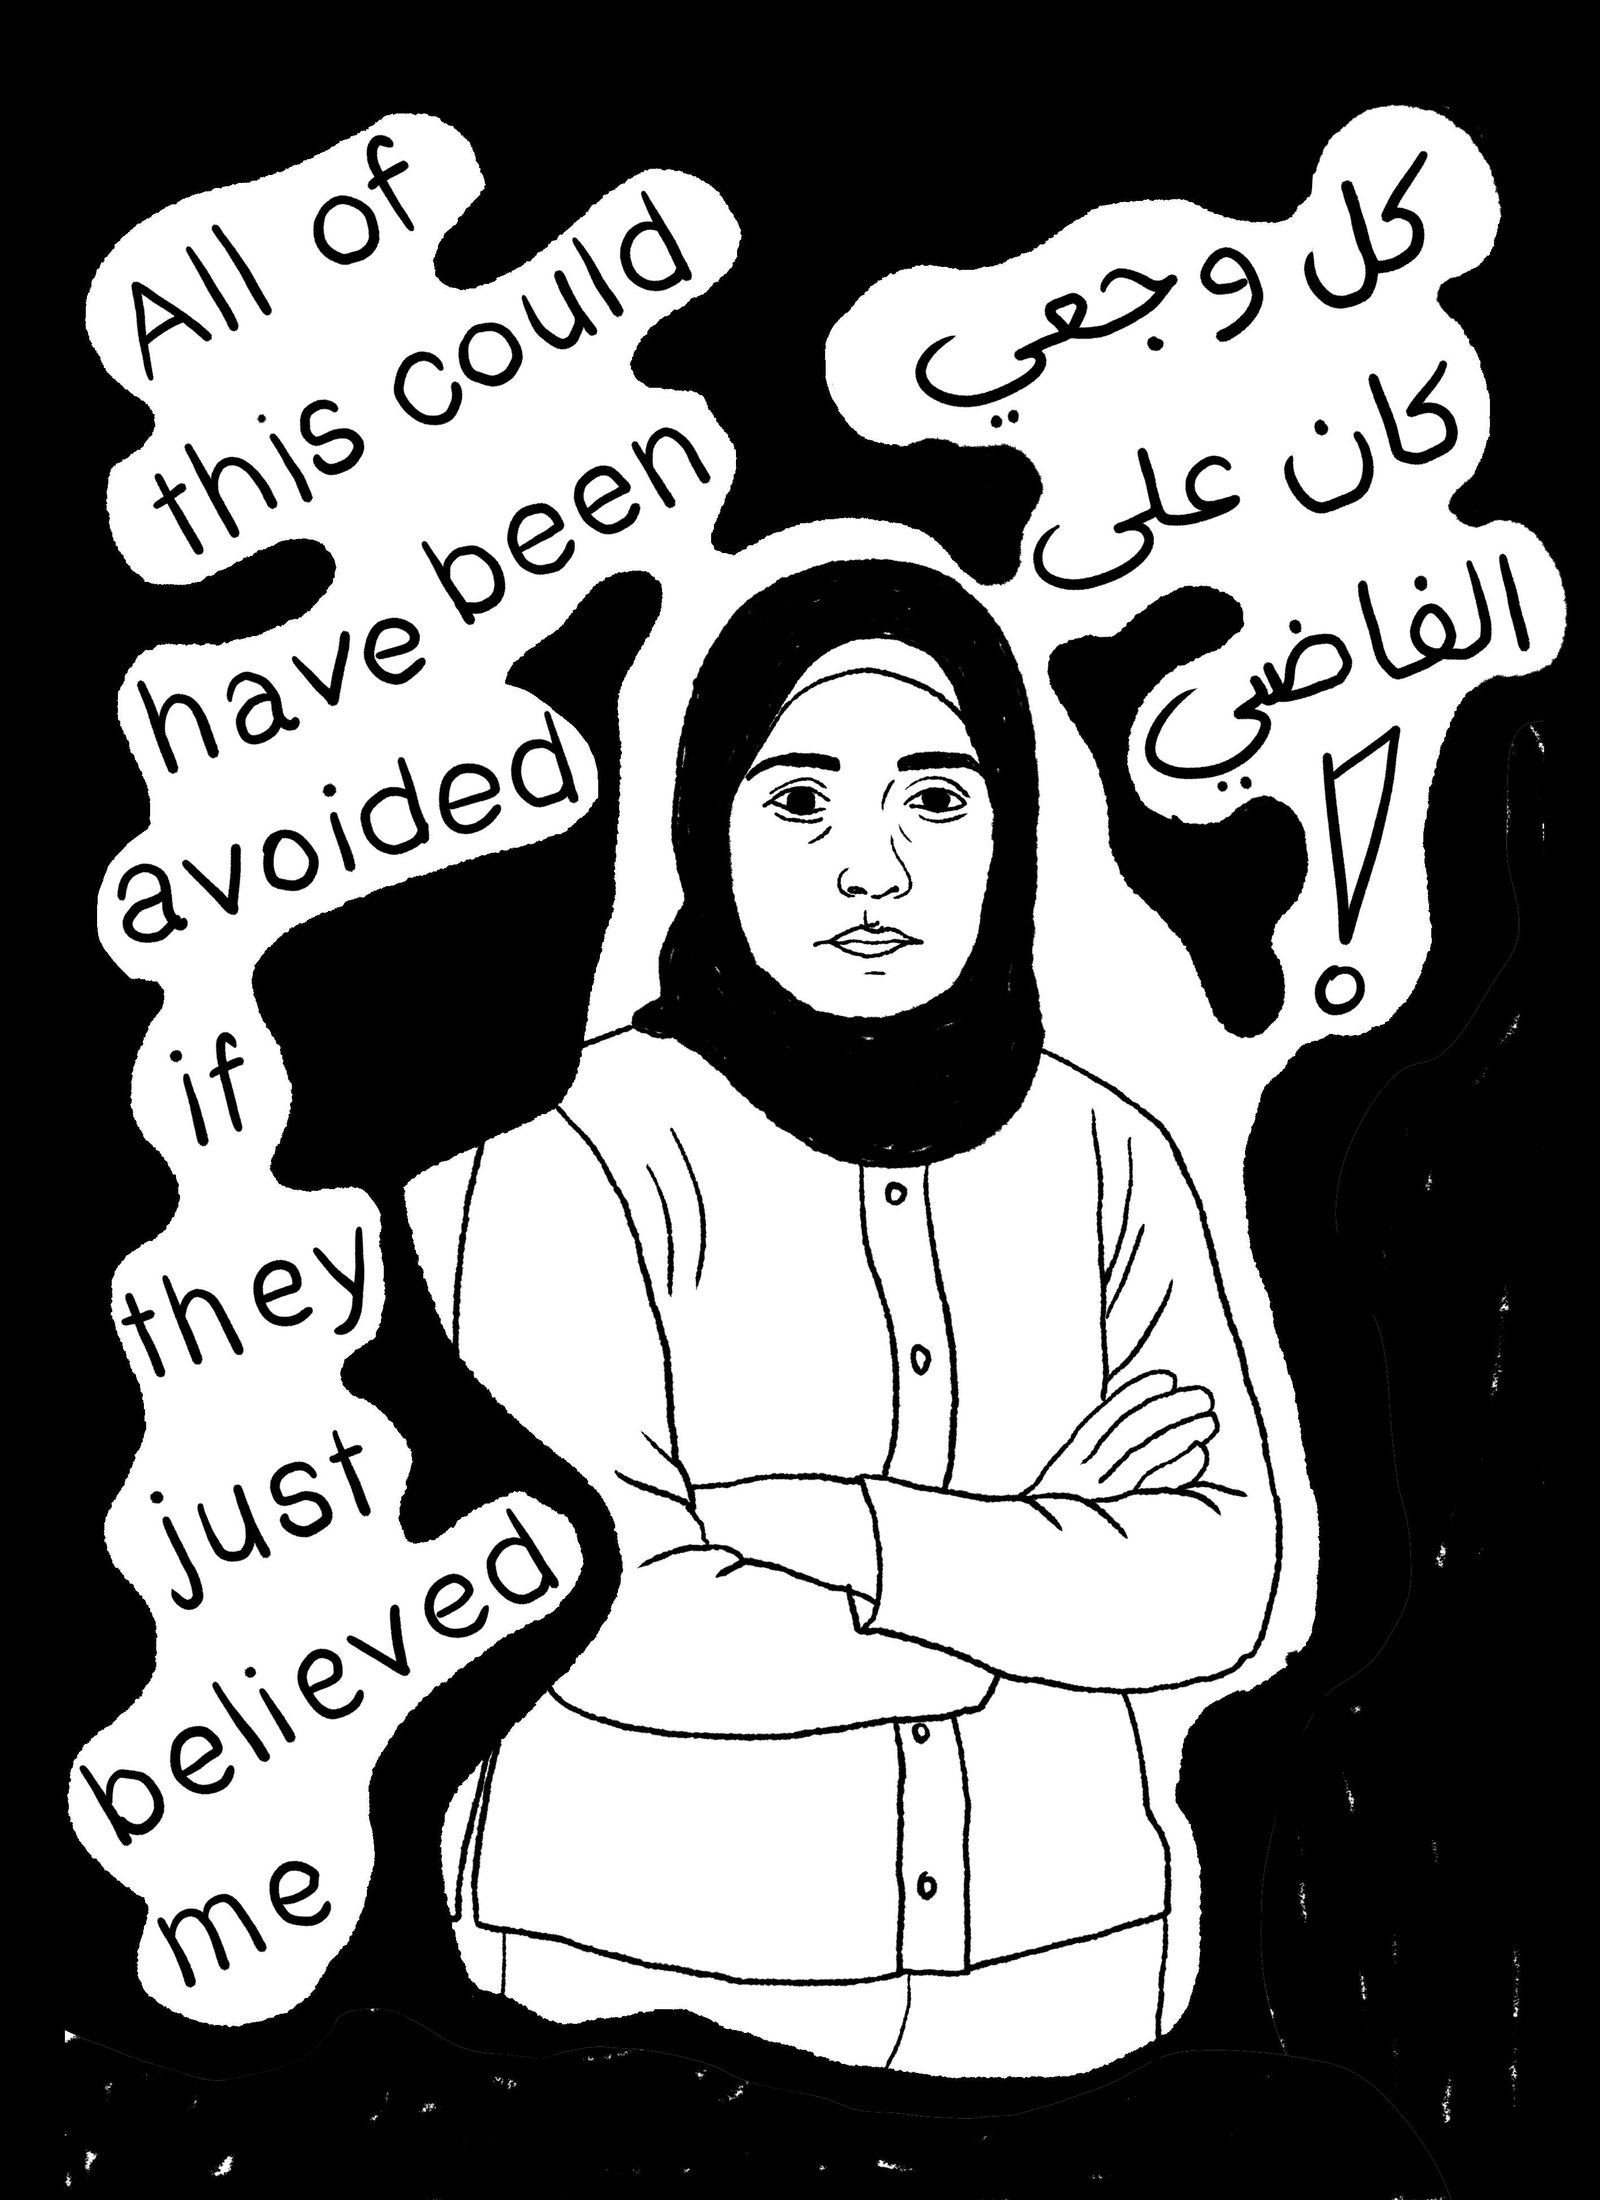

The P.O.V of the female patient, the reality of what is happening.

We believe you